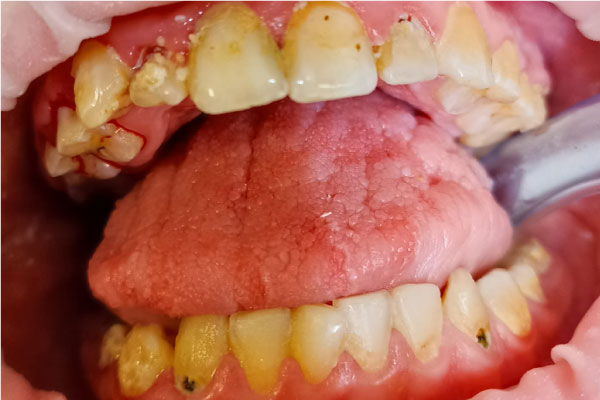

Фото ДО

Фото ПОСЛЕ

Профессиональная гигиена молочных зубов